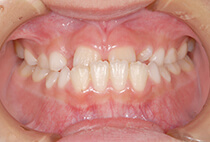

治療前

治療後

しっかり前歯を下げるために、インプラントアンカーを使用してコントロールしました。

かみ合わせが整うと咬筋の過緊張が改善。

過緊張による筋肉肥大も改善しフェイスラインもすっきりしました。